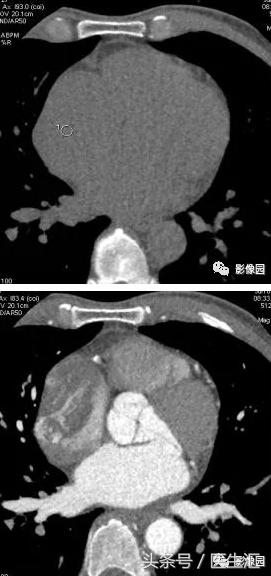

【基本资料】患者,男,42岁

【主诉】间断胸闷1年余。

【现病史】患者1年余前出现活动后胸闷,休息数分钟后可缓解,上述症状间断发作,行超声心动图示:右房占位病变、二尖瓣轻度关闭不全。

评论:右心房扩大,密度如常。增强扫描动脉期见欠规则结节状充盈缺损影,病变内见斑片状强化。